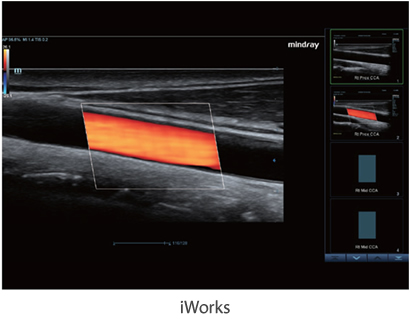

iWorks

iWorks le saca partido a los protocolos de trabajo estándar integrados para una mayor consistencia, reduciendo el tiempo de trabajo hasta un 50%. La herramienta altamente flexible y potente, es capaz de mejorar continuamente con las capacidades definidas por el usuario.